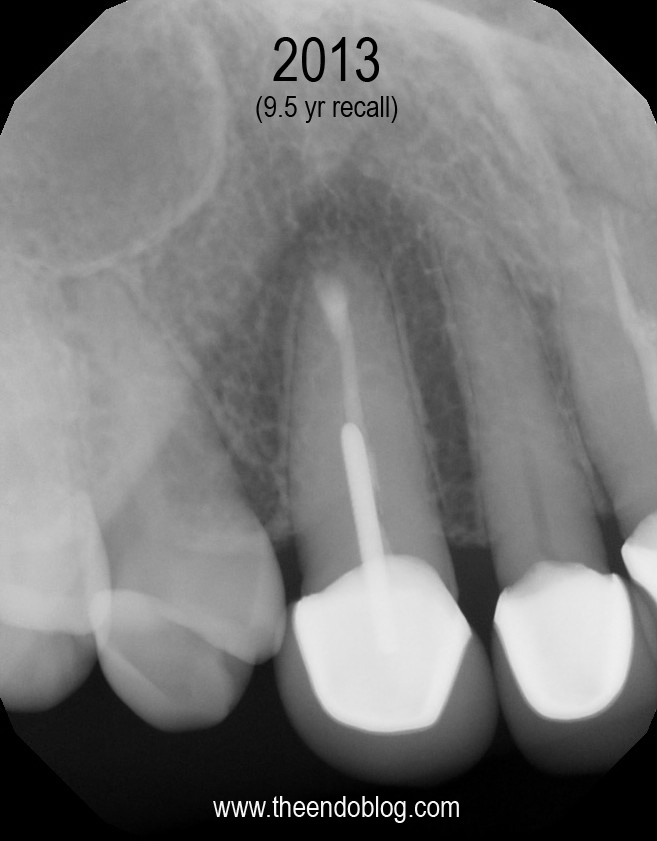

This patient has crowns on #6-#11.  Tooth #6 is causing a localized ache, affected by pressure and chewing. #6 is sensitive to percussion with normal probings. DX:  Prior RCT with Symptomatic Apical Periodontitis (SAP). The margins are suspicious, but apical surgery was chosen to address the infection without disturbing the existing crown.

Apicoectomy completed, no root fractures seen with microscope. MTA retrofill.

9.5 year recall.  Tooth is fully functional, asymptomatic with radiographic healing.  Apicoectomy has preserved the tooth and the periodontium for an extended period of time.